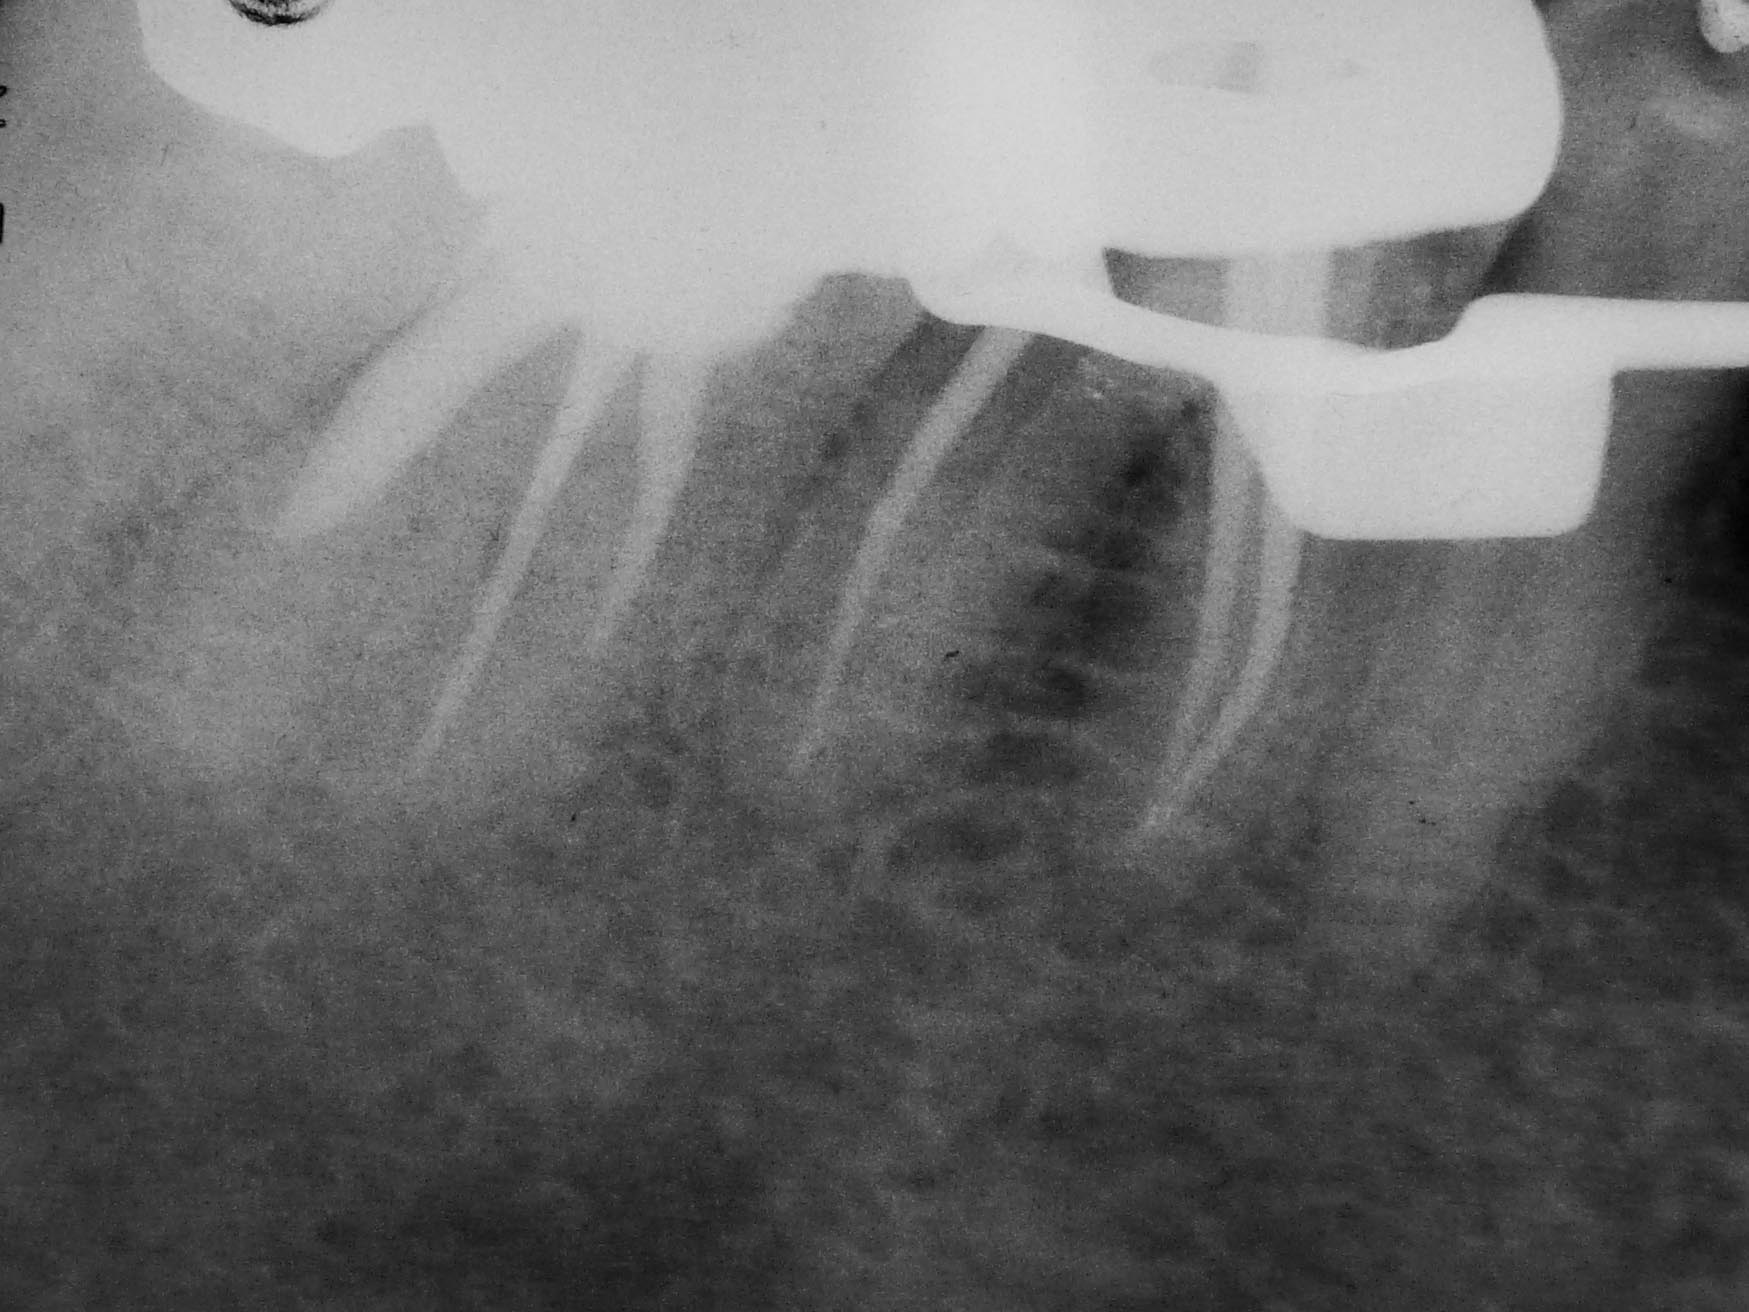

Rätselbild-4 Veröffentlicht 31. August 2009 am 1749 × 1312 in Shit happens: Das Rätselbild – Die Auflösung